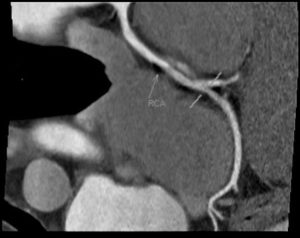

Пример томограмм МРТ сердца и сосудов

Определение изменений коронарных артерий, аорты требует процедуры с контрастированием. Внутривенная инъекция препарата помогает отслеживать внутреннее и внешнее состояние сосуда. Метод выявляет нарушения проходимости, участки сужения, места локализации атеросклеротических бляшек, тромбов.

Таким образом, МРТ сосудов и сердца не только делают, но и рекомендуют выполнять при подозрении на патологии миокарда, перикарда, сердечных клапанов. Обследование позволяет верифицировать расслоение стенки артерии (аневризма), тромбоэмболию сосуда. После внутривенного введения контраста удается выявить участки нарушения микроциркуляции, зоны сужения артерии.